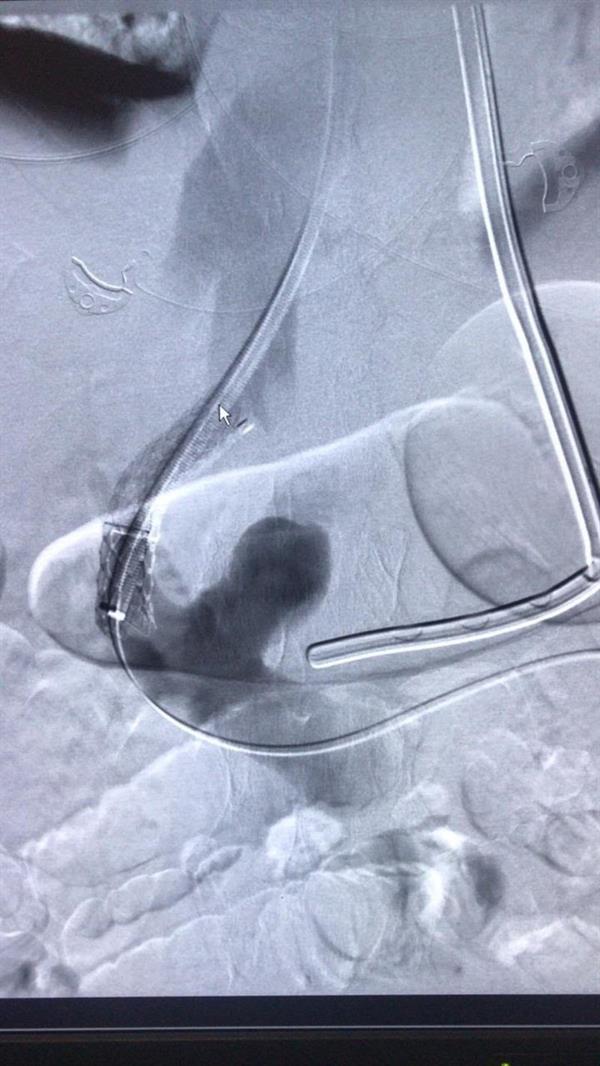

بعد تنويم المريض بقسم العناية المركزة، تمت استشارة قسم الأشعة التداخلية والقسطرة، حيث تم عمل تدخل عاجل عن طريق وضع دعامة وريدية موصلة بين الوريد الأجوف السفلي والوريد البابي لتقليل ارتفاع ضغط الدم بالوريد البابي ودوالي المعدة والمريء؛ الأمر الذي أدى إلى إيقاف النزيف، في عملية استغرقت نحو خمس ساعات توقف النزيف بعدها مباشرة وتحسن المريض في خلال أسبوع، ومن ثم خروجه من المستشفى، علمًا بأن قسم الأشعة التداخلية والقسطرة بمستشفى النور التخصصي الوحيد على مستوى صحة مكة والذي يخدم قطاعًا عريضًا من المرضى مواطنين وزائرين.